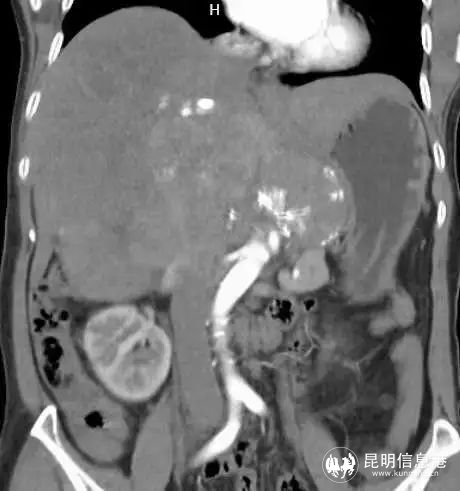

57歲的吳女士,從今年年初開始,感覺體力不斷下降,白天易疲勞,提不起精神,胃口也不好,體型日漸消瘦,不久出現(xiàn)右上腹隱約疼痛癥狀。家人送醫(yī)后CT檢查結(jié)果顯示:中、上腹巨大不均質(zhì)腫物,填塞肝門,貼壓膽囊、胰腺、右腎、門靜脈、下腔靜脈,考慮惡性。

圖為術前影像

患者入院后,省三院肝膽胰外科專家團隊經(jīng)過仔細檢查后發(fā)現(xiàn)該患者中上腹巨大不均質(zhì)腫物已經(jīng)填塞肝門,與肝實質(zhì)分界不清,貼壓膽囊、胰腺、右腎、門靜脈、下腔靜脈,手術操作的空間非常小。其次,患者身體基礎條件十分不好,長期高血壓,心肺功能極差,肝功能下降,手術難度極大。